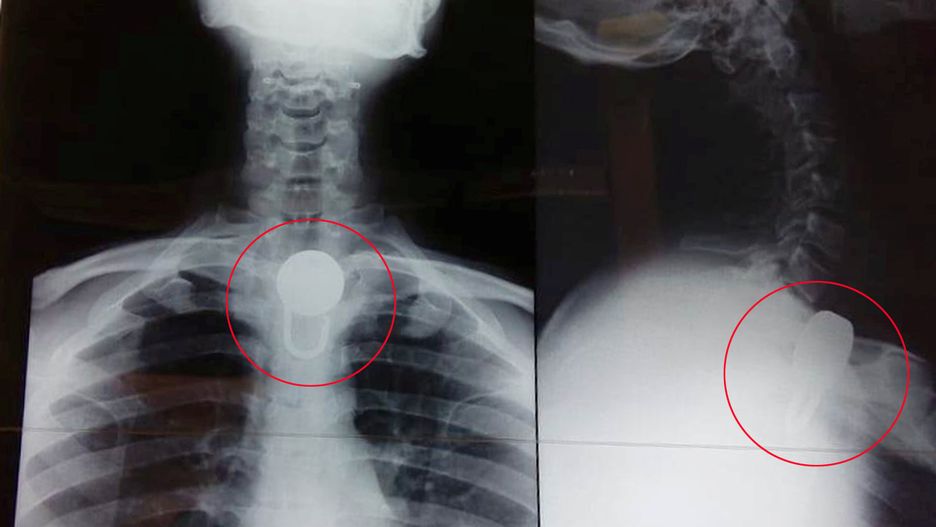

Mężczyzna z Indii połknął kłódkę o długości 6 cm. Zrobił to po tym, jak rodzina, ze względów bezpieczeństwa, zamknęła go w domu. Operacja usunięcia przedmiotu trwała aż kilka godzin.

Kłódka miała aż 6 cm szerokości. Po przywiezieniu Jumara do szpitala lekarze ze zdziwieniem odkryli, że przedmiot nie wyrządził w organizmie żadnych szkód. Był jednak zbyt duży, aby usunąć go nieinwazyjnie.

Kłódka miała około 6 cm i została mocno zaklinowana w przełyku. Nie można było jej usunąć za pomocą nieinwazyjnej procedury endoskopii – powiedział Dr Pradeep Jumar Singh, ordynator oddziału laryngologicznego.

Operacja usunięcia kłódki odbyła się 14 lutego. Zabieg odbył się w Rajendra Institute of Medical Sciences w Indiach. Trwał ponad 4 godziny i zakończył się sukcesem.

Pozostawieni bez innej opcji, aby uratować życie Jitendry, zdecydowaliśmy się na dość ryzykowną operację, aby usunąć ciało obce – dodał lekarz.